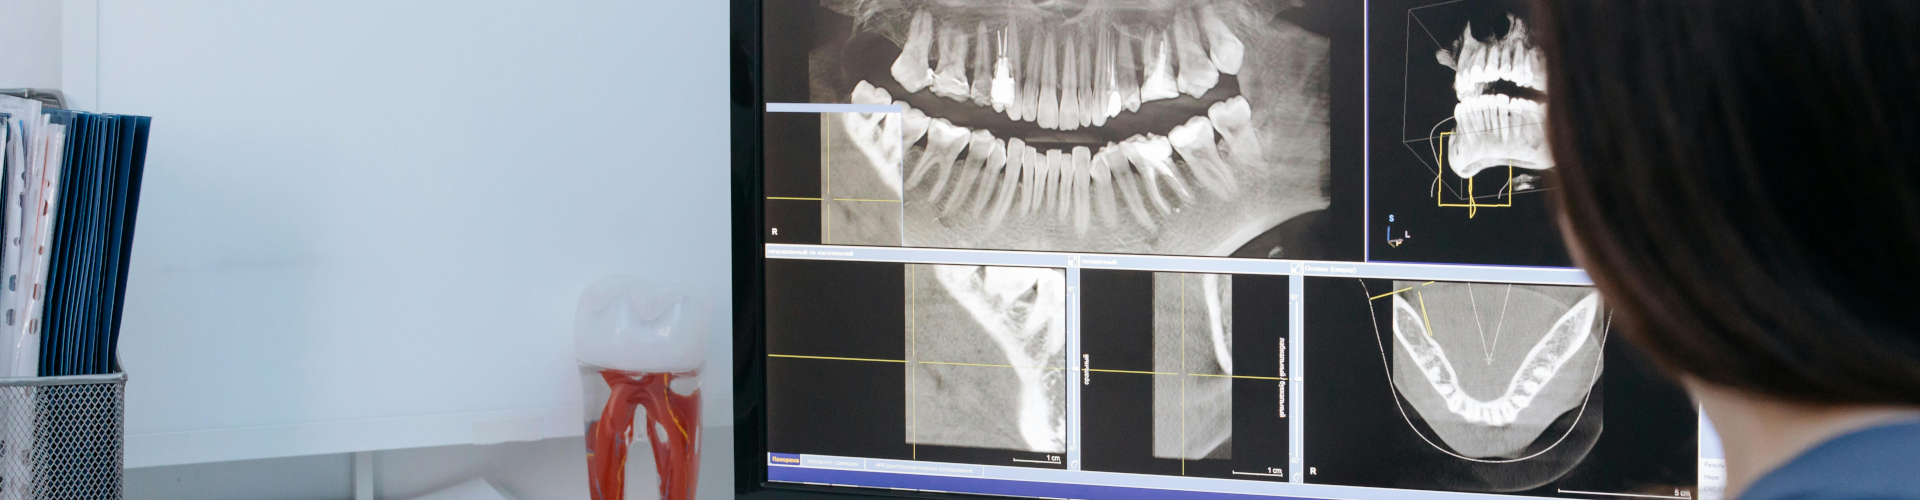

Panoráma röntgen (extraorális): A teljes fogsorról, állcsontról és arcüregről ad átfogó képet. Ideális általános állapotfelméréshez, fogszabályozás vagy implantátum beültetése előtt.